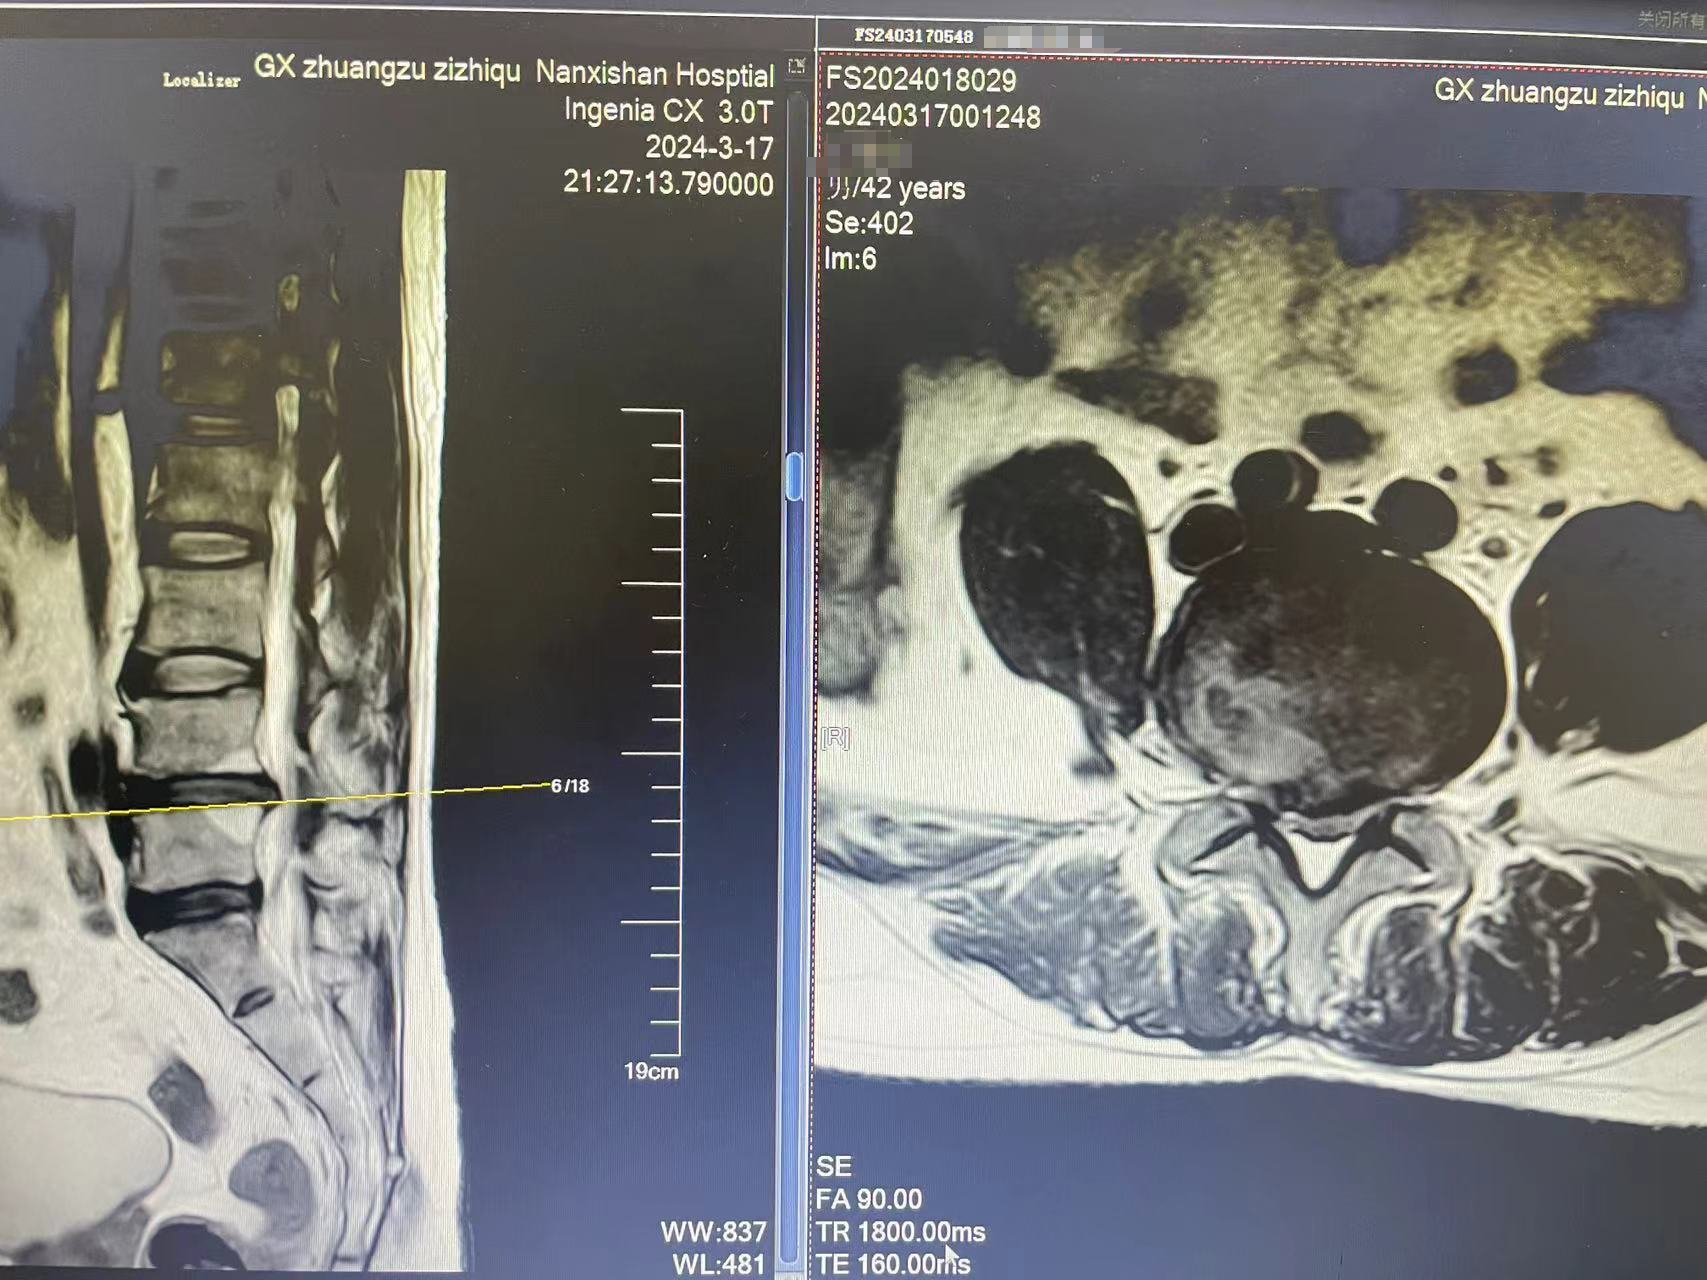

近日,一位来自龙胜县的 42 岁的王姓男子因长期受右下肢放射痛及麻木困扰,在广西壮族自治区南溪山医院接受了内镜下腰 4/5 椎间盘突出摘除术。手术在全麻状态下顺利进行。

据了解,该患者右下肢放射痛及麻木症状已持续三月有余,严重影响了其日常生活和工作。为彻底解决问题,患者选择就医并接受了手术治疗。手术由经验丰富的脊柱外科吴石奇主任医师及医疗团队在全麻下进行,采用内镜下腰 4/5 椎间盘突出摘除术。

手术过程中,医生凭借精湛的技术和严格的手术要求,成功摘除了突出的腰椎间盘,解除了对神经根的压迫。术后,患者接受了消炎止痛、营养神经等对症支持治疗,病情得到了控制。